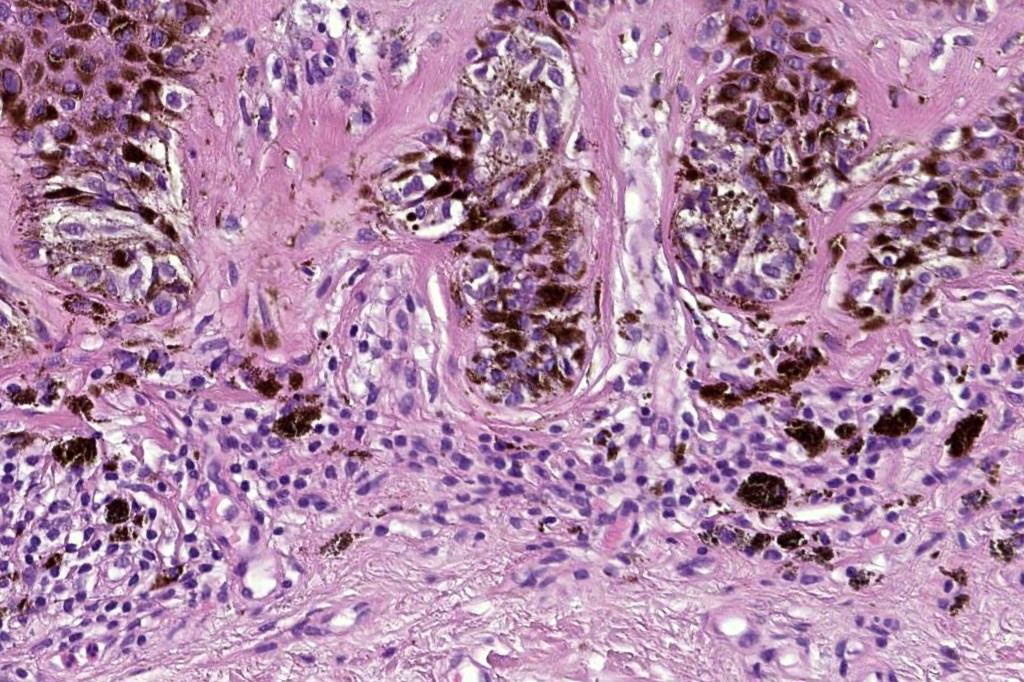

•Host response- eosinophilic & lamellar fibroplasia, increased vascularity, lymphocytic infiltration & pigment incontinence

Dysplastic nevus is sometimes confused with early/evolving Reed nevi. The presence of an almost pure population of uniform, spindled melanocytes, often heavily pigmented nested lesion forming a flattened lower border make the distinction fairly straightforward. Reed nevus is symmetrical & circumscribed.

Dysplastic nevus with early melanoma